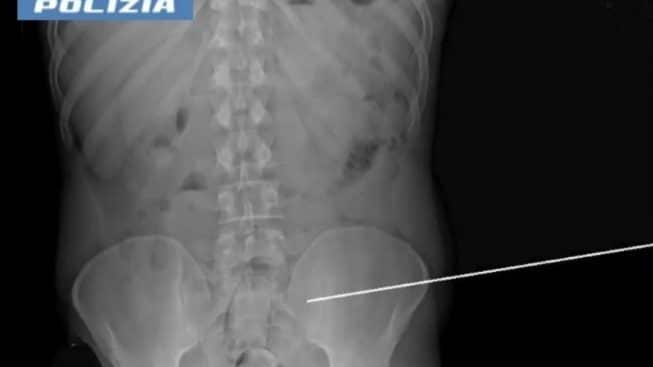

A fronte di ispezioni sulla persona e sui bagagli risultate sempre negative, l’uomo, al rientro dall’ultimo permesso, è stato condotto all’ospedale Santissima Annunziata del capoluogo jonico n quale è stato sottoposto a una radiografia. L’esame ha evidenziato che nell’addome del detenuto vi erano due corpi estranei, due palloncini, appunto, contenenti rispettivamente 50 e 100 grammi di hashish. Il 27enne è stato arrestato e riportato in carcere.